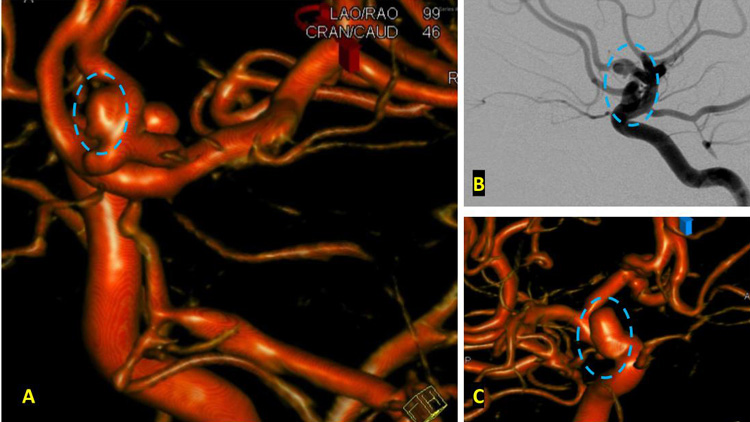

On admission, she presented as a GCS 3, was intubated, and stabilized hemodynamically in preparation for emergent catheter cerebral angiography, which revealed 2 discrete geographically located aneurysms – 1) Anterior Communicating and 2) Right ICA Supra-Clinoid Segment. (Figure 2.)

The Pattern of Hemorrhage was diffuse and generalized. On more careful analysis, however, there appeared to be focal hemorrhagic clot within the anterior inter-hemispheric fissure which raised greater suspicion for the Anterior Communicating Aneurysm as the source of hemorrhage. Although Acom Aneurysm was smaller, it’s irregular shape and eccentric “nipple” suggested potential rupture point. (Figure 3.)

After careful measurements of the parent vessels, aneurysm sac, and aneurysm neck, we decided to proceed with Primary Coil Embolization of the Acom Aneurysm first, followed by the Right ICA Aneurysm next. Despite greater suspicion in the Acom region, a significant level of uncertainty remained, and we felt it was better to secure both aneurysms if capable of being performed safely. (Figure 4.)